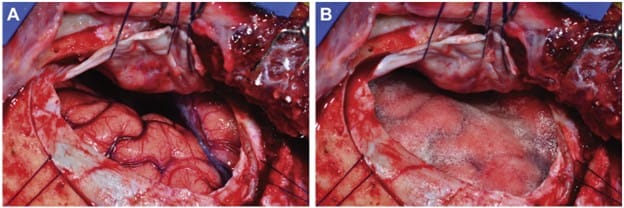

Figure 2. (A) Exposed cortex after haemostasis during right pterional craniotomy.

(B) Thin gelatin sponge placed over the cortex to separate the dura and protect it during closure.3